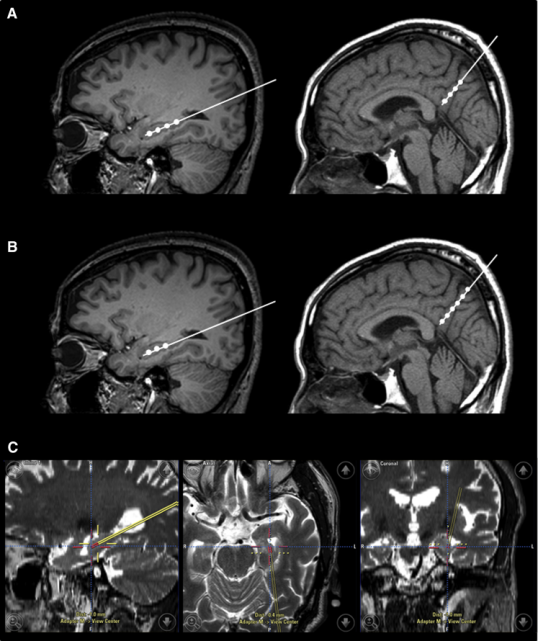

2015年,韓國(guó)首爾三星醫(yī)療中心招募了9名輕度至中度癡呆的阿爾茨海默氏病患者。Kim對(duì)9名患者進(jìn)行了一項(xiàng)立體定向注射間充質(zhì)干細(xì)胞的I期臨床試驗(yàn)。

三名患者接受低劑量(1.0×107細(xì)胞/2 mL),6名患者接受高劑量(3.0×107hUCB-MSC 的細(xì)胞/2 mL) 。9名患者進(jìn)行了三次干細(xì)胞注射(每隔4周一次)。

干細(xì)胞立體定向注射患者的右海馬體和右前丘盤

在之后長(zhǎng)達(dá)36個(gè)月的跟蹤研究期間, 沒有患者出現(xiàn)嚴(yán)重的不良事件。由此可見, 干細(xì)胞治療阿爾茲海默癥是可行、安全且耐受性良好的。